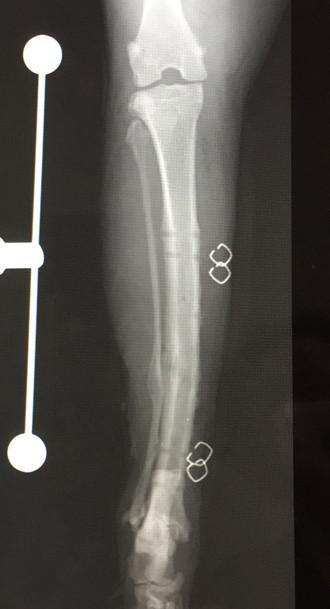

4月15日 手術から9ヶ月 後

札幌病院、経過観察、骨形成OK